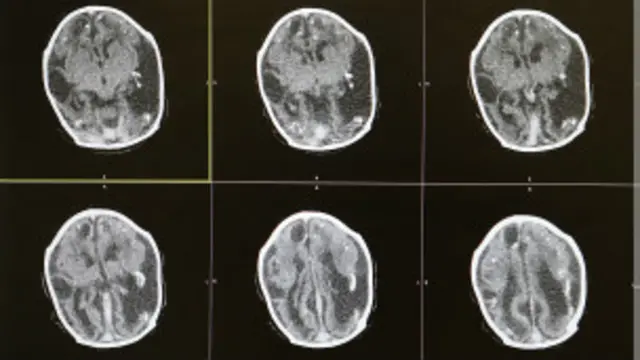

- 7. ¿Provoca daño cerebral?

Algunas infecciones, como la rubéola, pueden dañar el cerebro de bebés en desarrollo durante el embarazo.

Sin embargo, no tenemos información sobre cómo el zika podría entrar en contacto con la placenta o afectar al crecimiento del cerebro del feto.